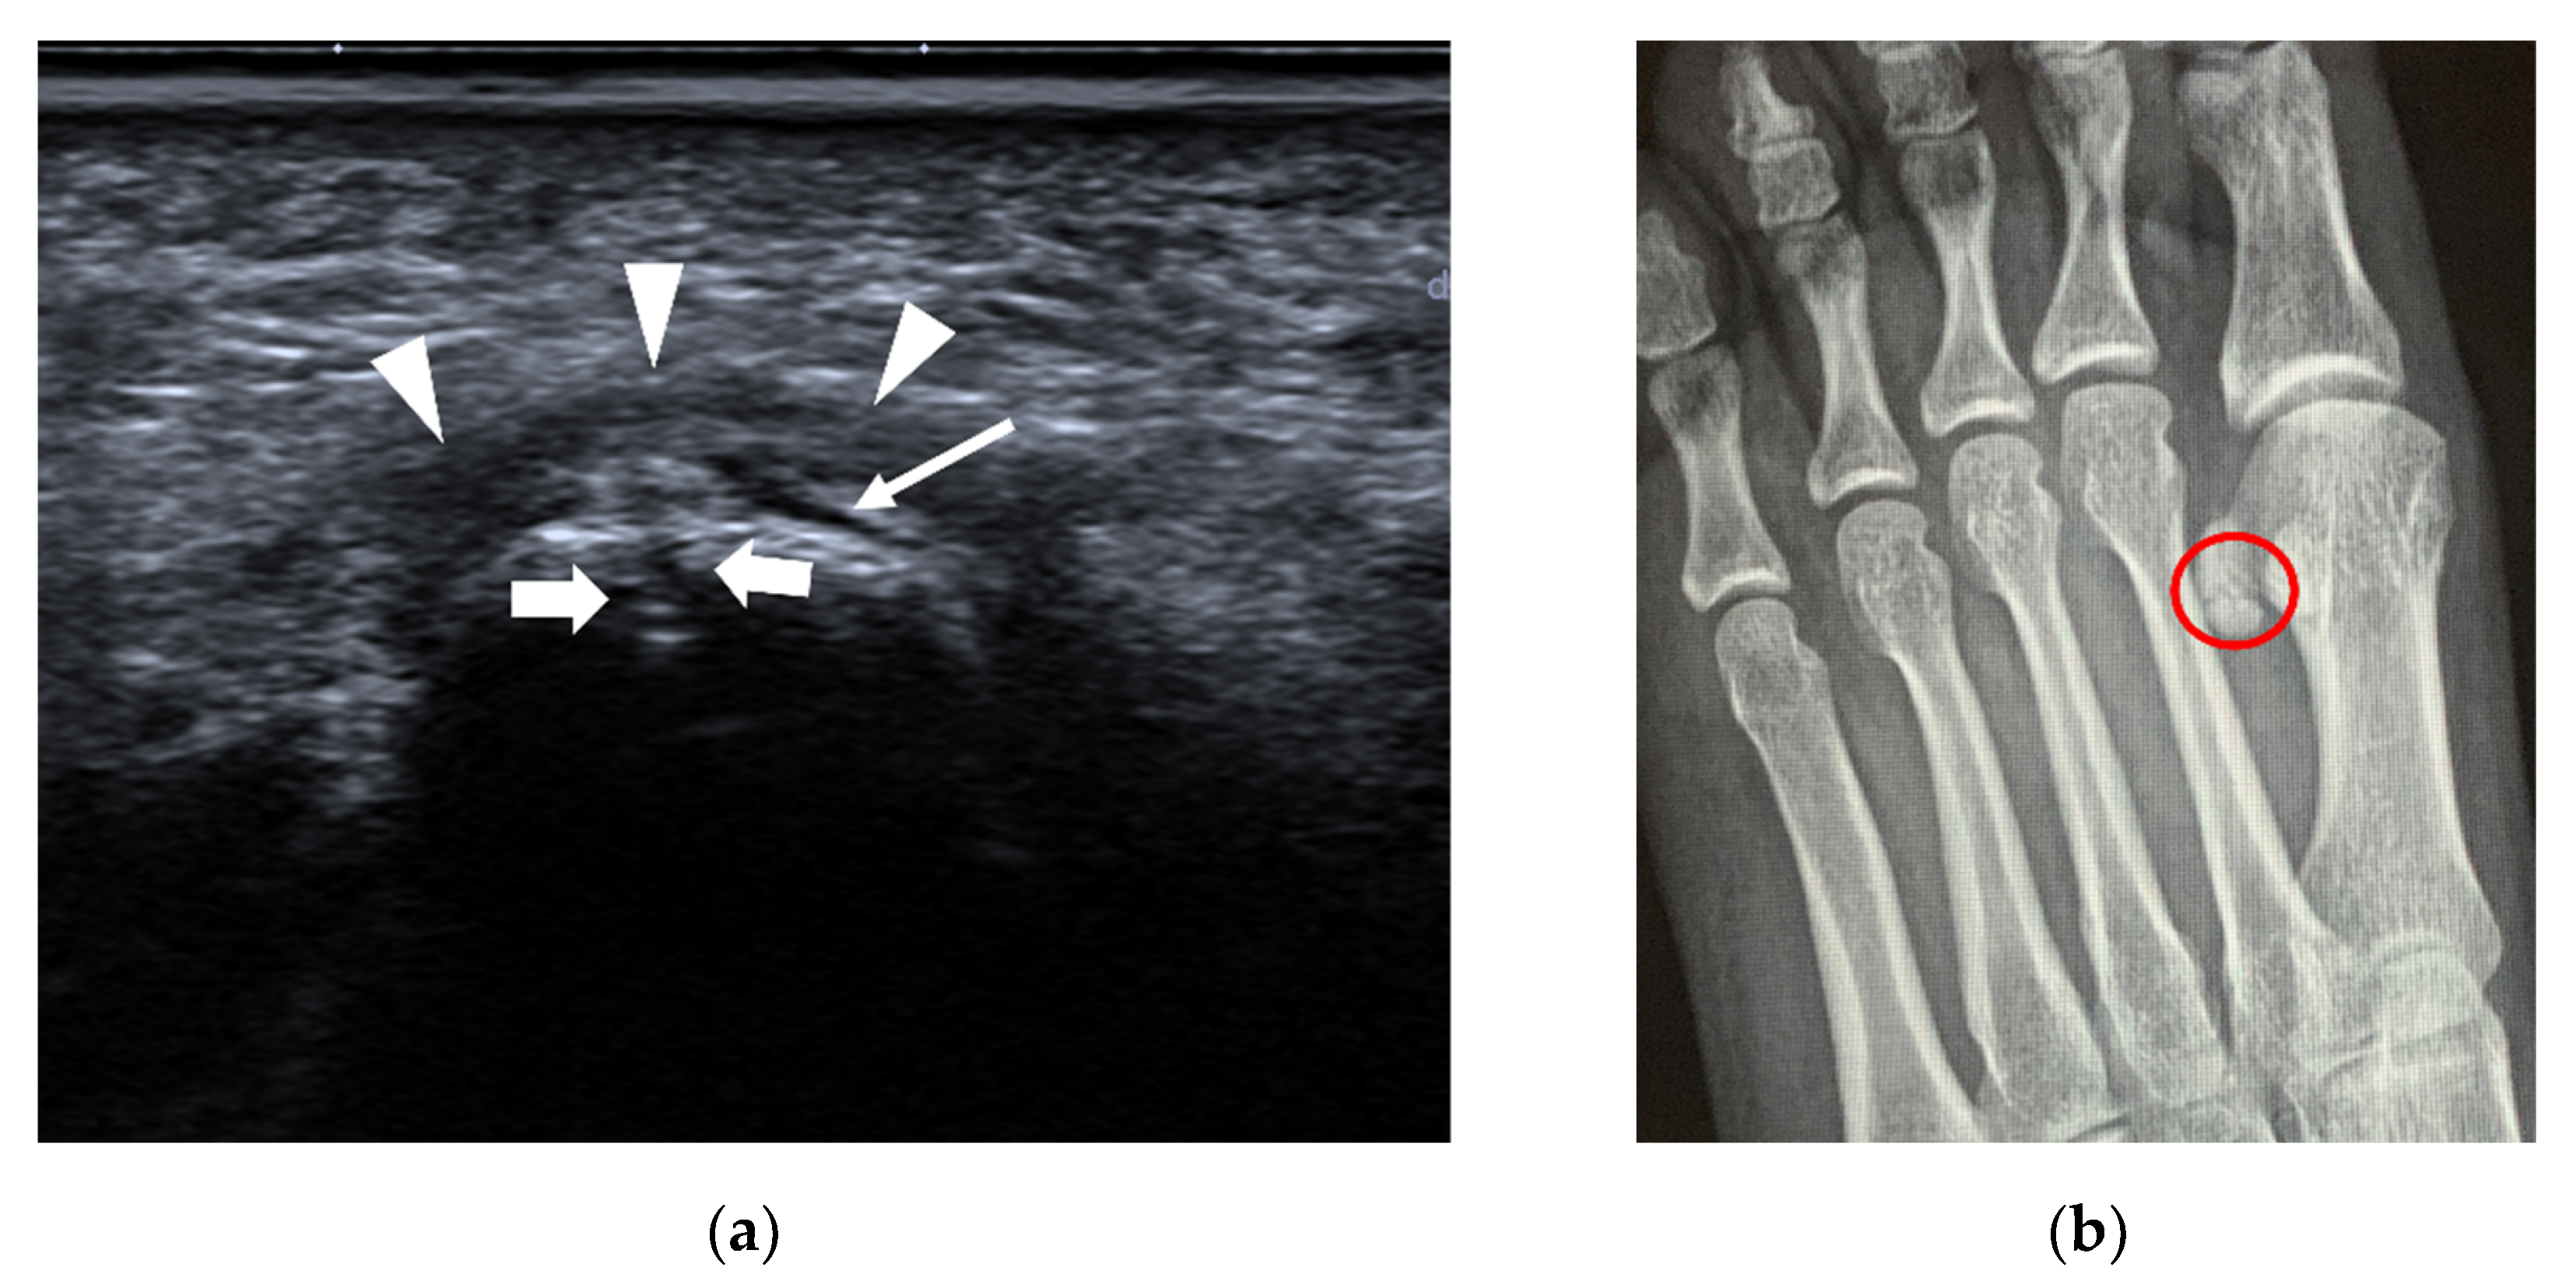

4.1.3. Stress Fracture

| Stress fracture | 2nd and 3rd metatarsals | periosteal lifting or cortical disruption, hypoechoic hematoma above the cortical bone |